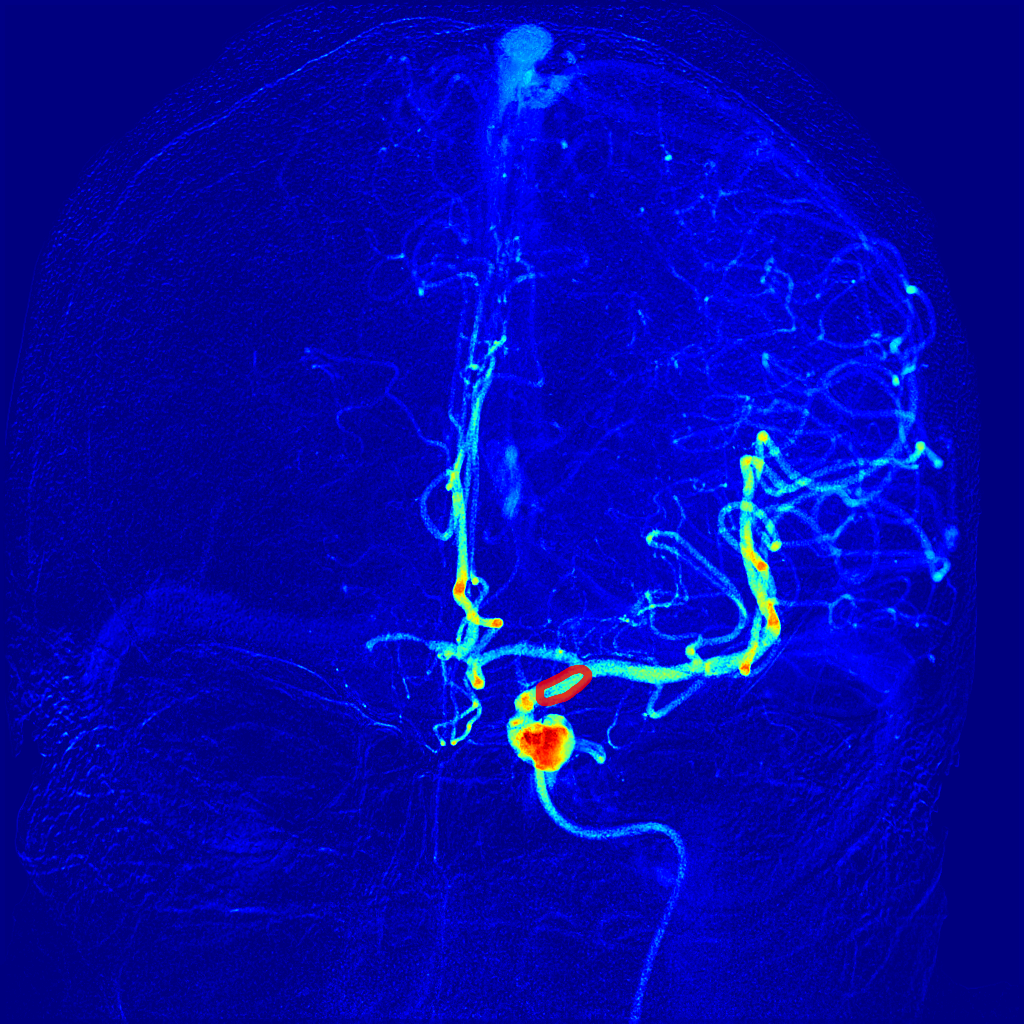

Automatic perfusion imaging in cerebral Digital Subtraction Angiography

Recent work on perfDSA demonstrates the potential of fully automatic and quantitative frameworks for perfusion analysis on DSA, analagous to more established modalities such as CTP and MRP. We are currently validating perfusion DSA to assess its clinical applicability, with the goal of enabling real-time decision-making during thrombectomy.